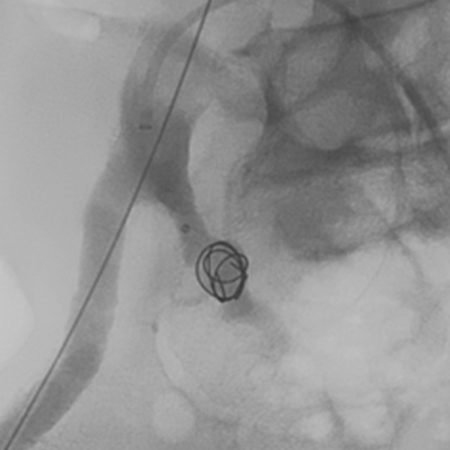

Peripheral embolization

Peripheral and neurovascular embolization with Trellix